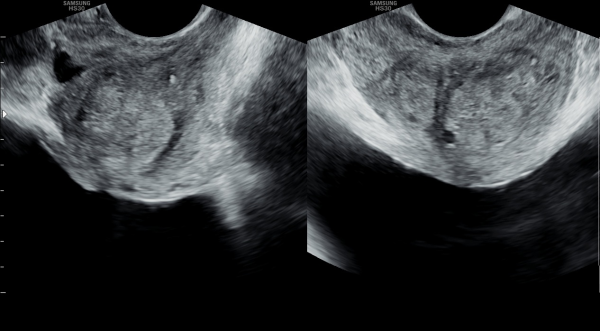

수개월 전부터 고혈압(내원 당일 170/100)과 전립선 약만 복용중 우연히 검사한 경직장 전립선 초음파 검사상 전립선의 비대와 결절 그리고 사정관낭종과 사정관이 탈락된 상피세포로 좁아져 정낭의 순환 장애를 일으키는 경직장 전립선 초음파 사진입니다.(NIH :15)

This transrectal prostate ultrasound image was taken during the patient’s first visit.

The patient had been taking medication only for high blood pressure (170/100 mmHg on the day of the visit) and prostate symptoms for several months. During a routine examination, this ultrasound study was performed.

The image shows enlargement of the prostate with nodules, as well as an ejaculatory duct cyst. The ejaculatory duct is narrowed by shed epithelial cells, reducing its diameter by approximately 60%.

This narrowing is causing impaired circulation of the seminal vesicles, which may be related to the patient’s symptoms (NIH symptom score: 15).